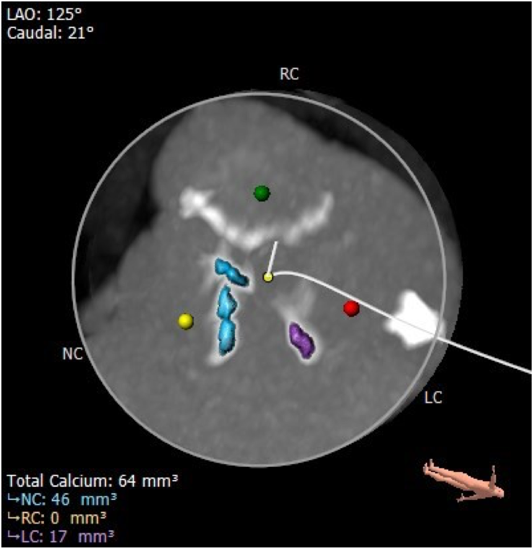

主动脉根部评估: